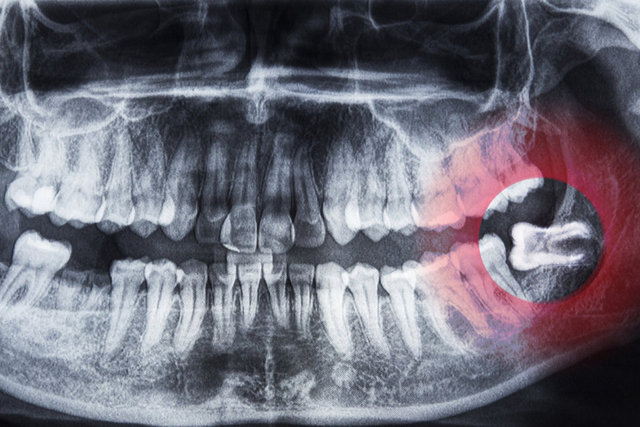

YİRMİLİK DİŞ

Yirmilik dişler eskiden yaşayan insanlar için oldukça önemliydi. Ancak artık oldukça nadir görülen bir vücut özelliği.